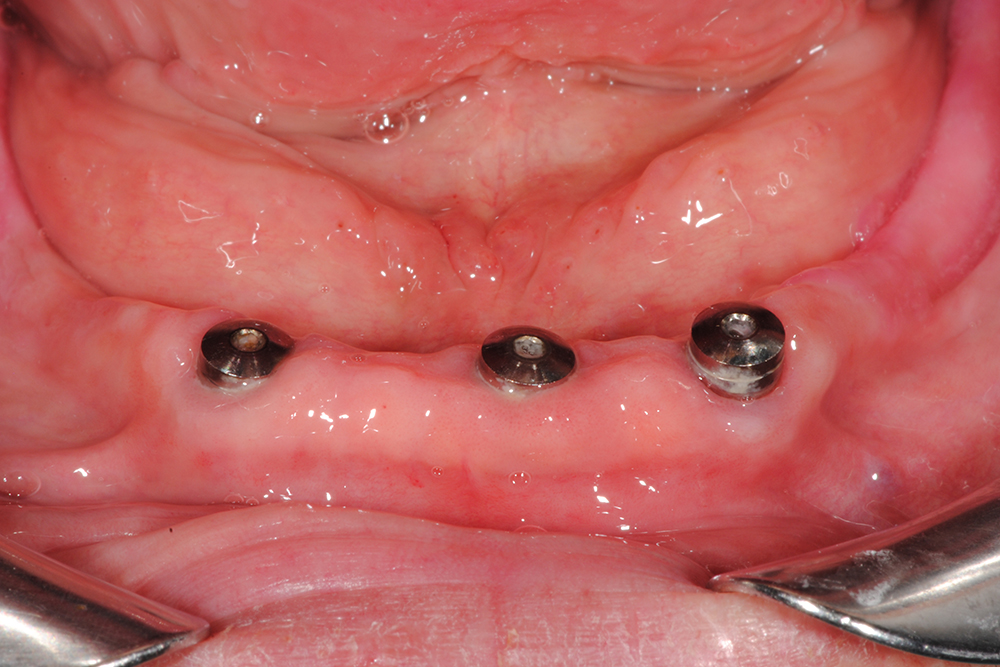

Ripristino dell’arcata superiore ed inferiore su overdenture su barra